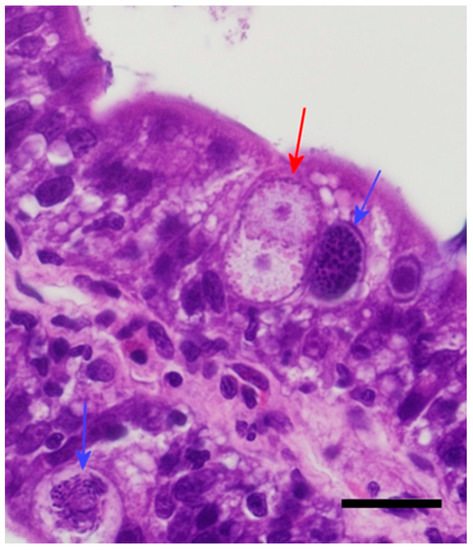

3.2. Pathogenesis of Isospora Amphiboluri